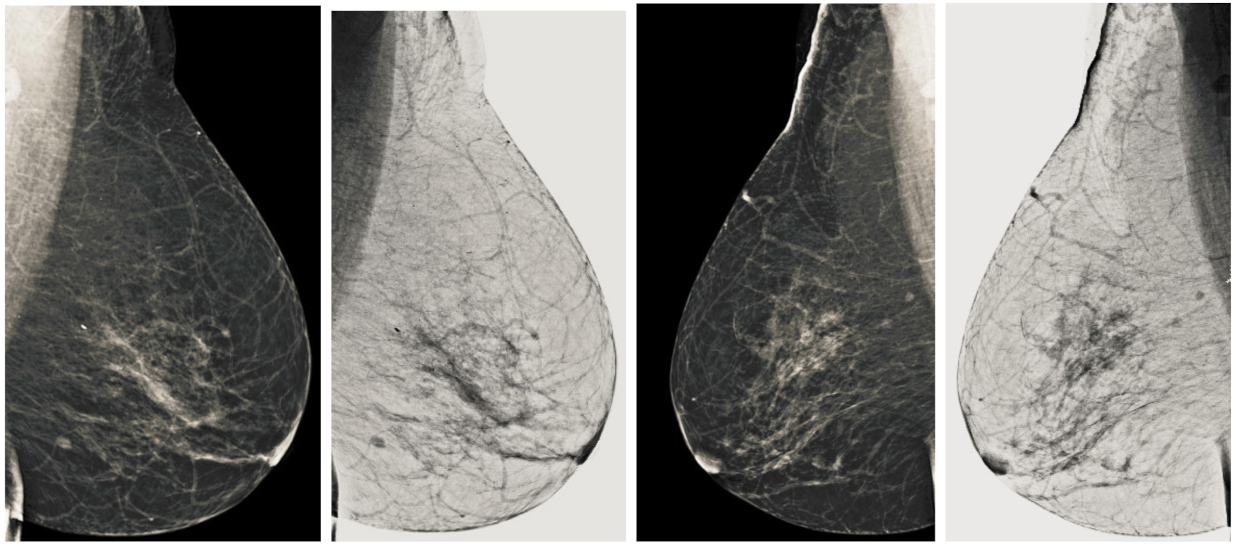

We also measured the PSNR, the image contrast, and the EME of each category of databases, as we analyzed the image in terms of visual observation. The Table 3 shows the performance of our proposed image enhancement method. It can be seen from the Table 3 that our proposed method improved PSNR, contrast, and EME, and this also shows that our method can work on every category of BI-RADS. Because many techniques do not work on higher grade BI-RADS due to the complexity and the images are not of good quality. We obtained an average improvement in PSNR, contrast, and EME in the Table 4. For more observations, we analyzed the visual image of each category and we analyzed the CC and MLO of each category as shown in the Figure 7, Figure 8, Figure 9, Figure 10, Figure 11, Figure 12, Figure 13, Figure 14, Figure 15 and Figure 16. From the figures, every detail of image of every category can be observed, leading to better segmentation of the abnormal region. This image enhancement technique can be used as preprocessing steps for the detection of breast cancer. It is a very fast processing algorithm and it takes on 21.13 s. It gives opportunity to medical experts to analyze the mammogram images very quickly to propose the timely treatment.

Figure 7.

Analysis of CC view of BI-RADS-1 mammogram images.

Figure 8.

Analysis of MLO view of BI-RADS-1 mammogram images.

Figure 9.

Analysis of CC view of BI-RADS-2 mammogram images.

Figure 10.

Analysis of MLO view of BI-RADS-2 mammogram images.